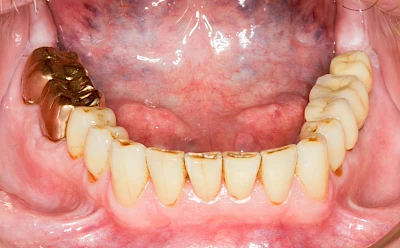

Implantate: Kronen & Brücken

Fehlen einzelne Zähne und die Nachbarzähne sind unbeschadet oder gut zahnärztlich versorgt, werden immer häufiger Implantate gewählt, um die Lücken zu schließen. Auch bei größeren oder verteilten Lücken, wenn keine herausnehmbare Prothese gewünscht ist, werden Implantate für Kronen- bzw. Brückenversorgungen gesetzt. In Einzelfällen entscheiden sich sogar zahnlose Patienten für eine festsitzende Versorgung auf Implantaten.

Varianten zur Verankerung von festsitzendem Zahnersatz auf Implantaten